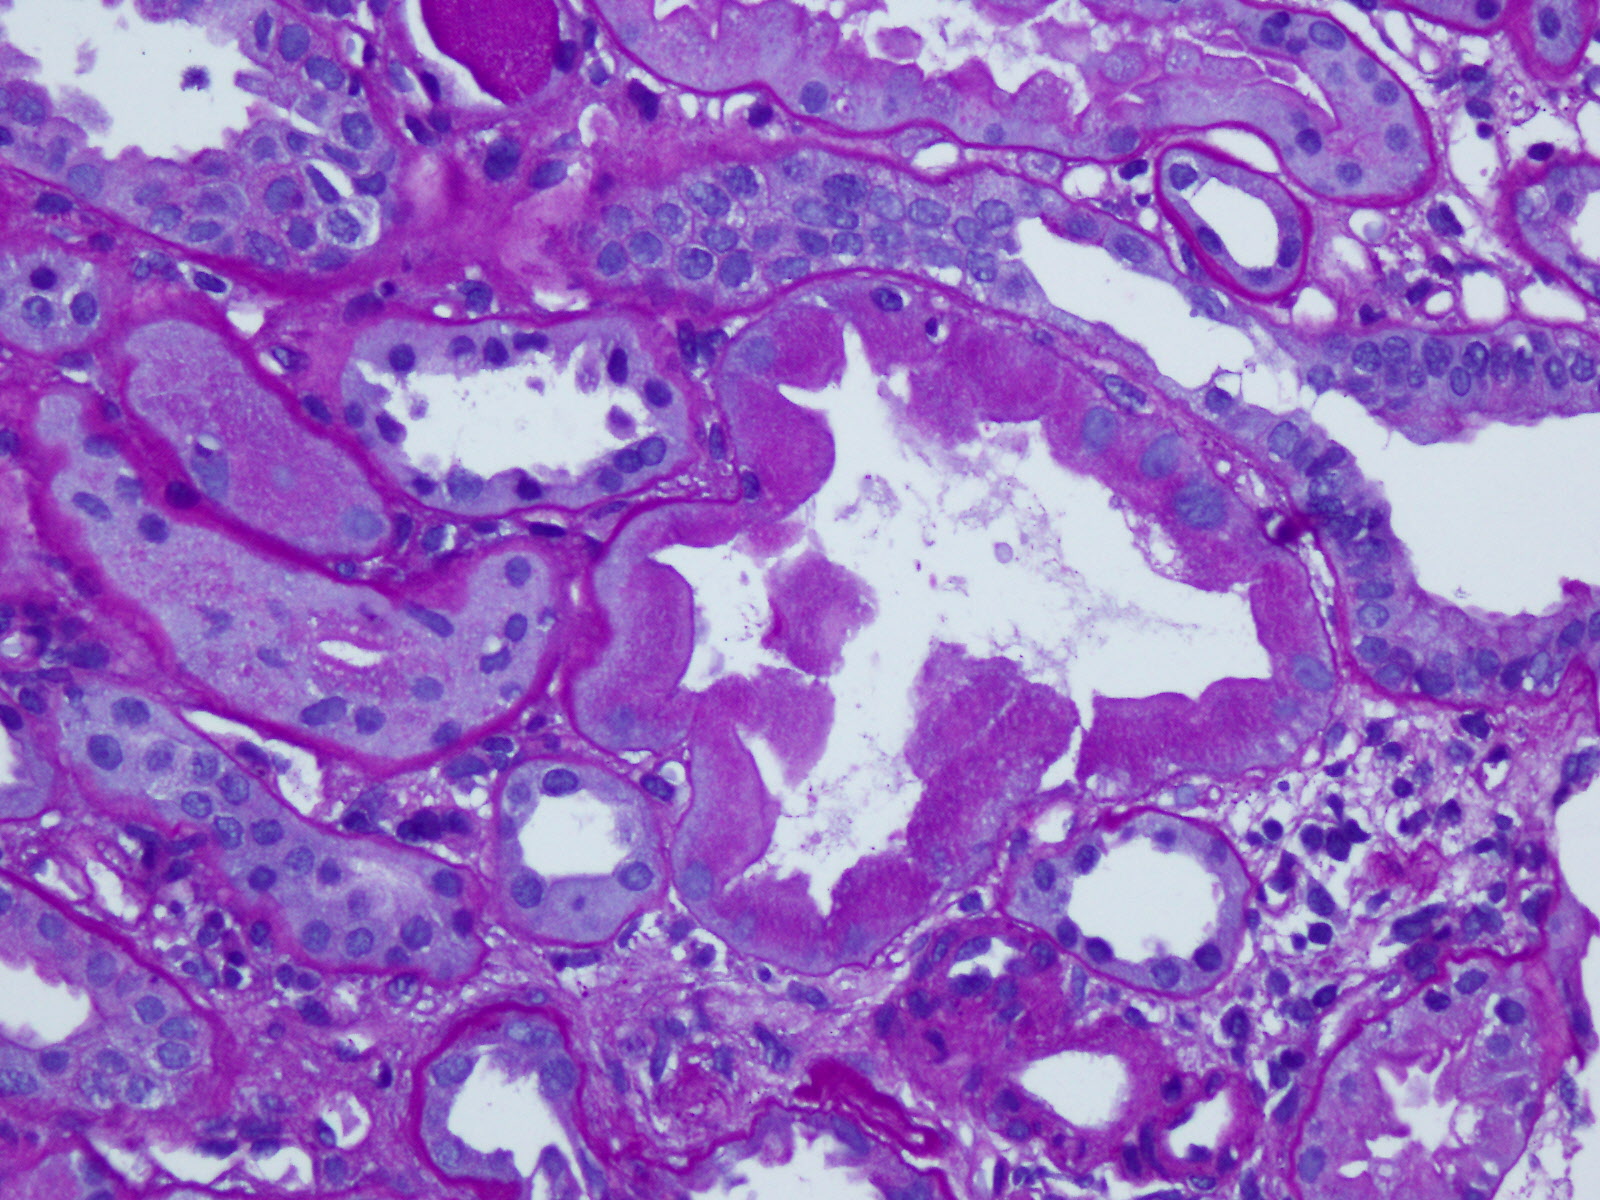

In general, assuming 18 gauge cores, try to allocate

- 0.3cm - 0.5cm of cortex with glomeruli for Michel’s, IF

- 1.0cm to 3.0cm of cortex with glomeruli for formalin, LM

- 0.3cm - 0.5cm of cortex with glomeruli for glutaraldehyde, EM

The tissue will be entirely safe in any of these fixatives for at least several days.

Refrigeration is not required.

When a limited sample is obtained, allocate to Michel's and formalin. We will re-allocate for EM.